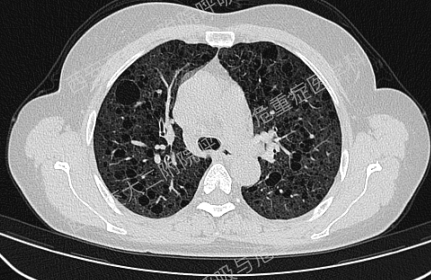

上图与Case 2比较相似,所以诊断LAM没有问题,还需进一步排查系散发型还是结节性硬化症累及。

影像学评估发现患者多系统受累(肝脏错构瘤、双肾血管平滑肌脂肪瘤、颅脑多发异常信号结节)。追问病史,患者本人无皮疹、癫痫及智力低下;患者儿子有面部皮脂腺瘤,无癫痫及智力低下,胸腹部CT未见异常,皮肤科已确诊结节性硬化症;患者女儿面容及智力均正常;建议患者进一步行TSC基因检测,结果回报TSC2突变,结节性硬化症诊断明确。